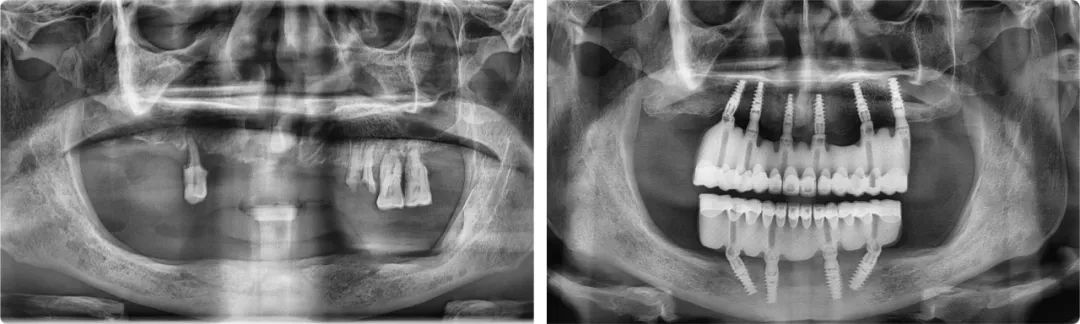

王旭東首例全口種植案例術(shù)前術(shù)后全景片

2019年12月31日,拔牙、植入10顆種植體、取模、戴牙(臨時修復體)、調(diào)整,當所有治療程序全部完成,時針已滑過零點。這次跨年手術(shù)是王旭東完成的第一例全口種植修復治療,也是陳醫(yī)生過得最開心的一個元旦。新的一年,他終于可以正常吃飯、說話,無所顧忌地大笑了。